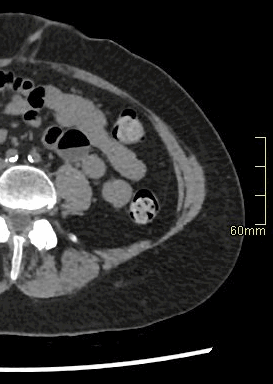

CT Hip Contrast- Soft tissue window (axial)

SCAN RANGE: Entire pelvis from iliac crest to below lesser trochanter (Multi-planar reconstructions only of affected hip).

CT Hip Non Contrast- Bone window (axial)

CT Hip Non Contrast- Bone window (coronal)

CT Hip Non Contrast- Bone window (sagittal)

CT Hip Non Contrast- Soft tissue window (axial)

*Extra 3D Reconstructions Available